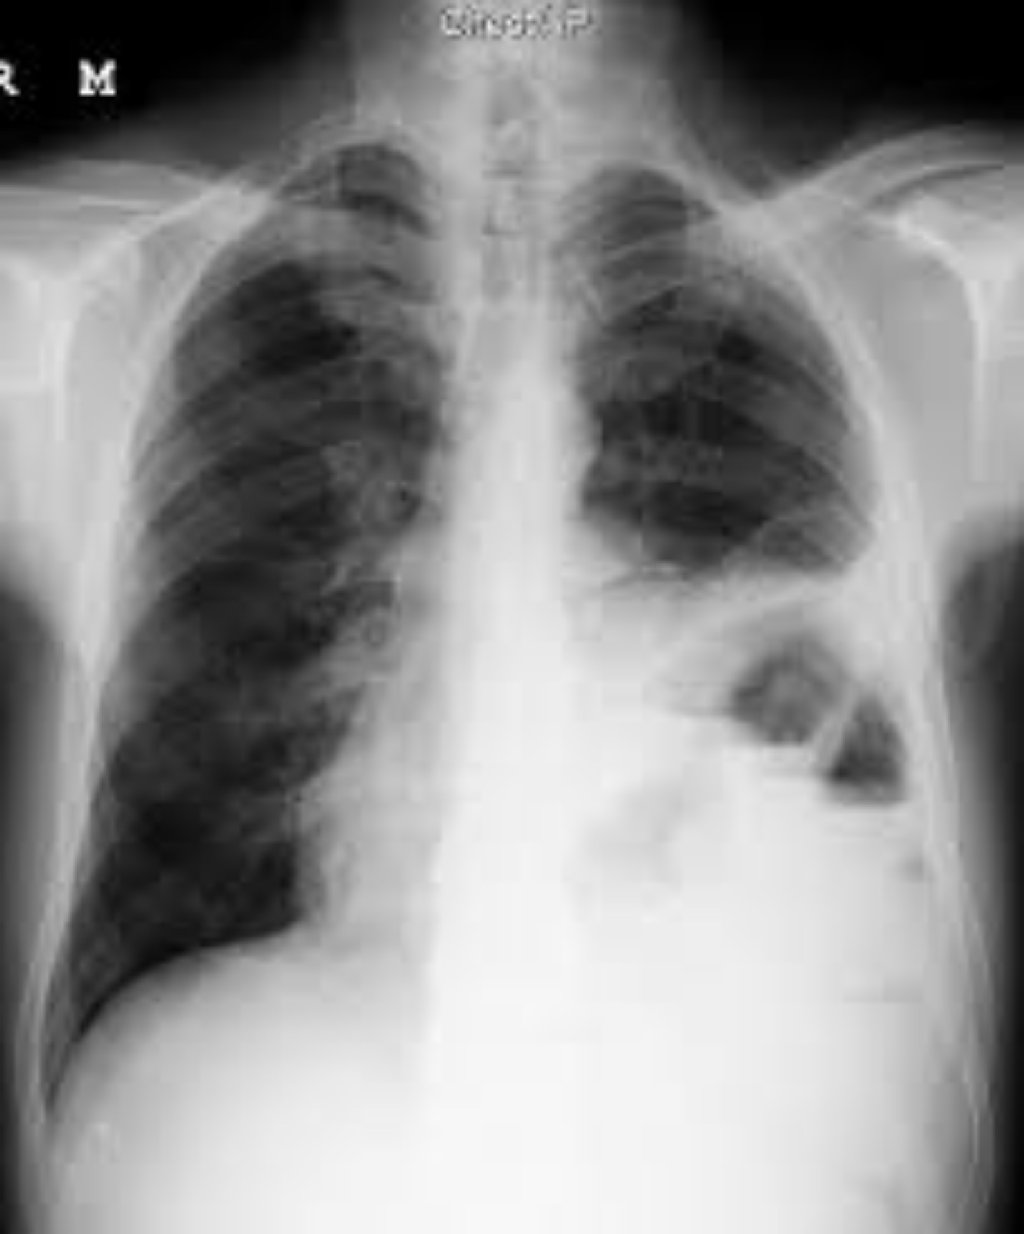

Yuxu apnesinin iki növü var: obstruktiv yuxu apnesi (OUA) və mərkəzi yuxu apnesi. OUA, yuxu zamanı y ...